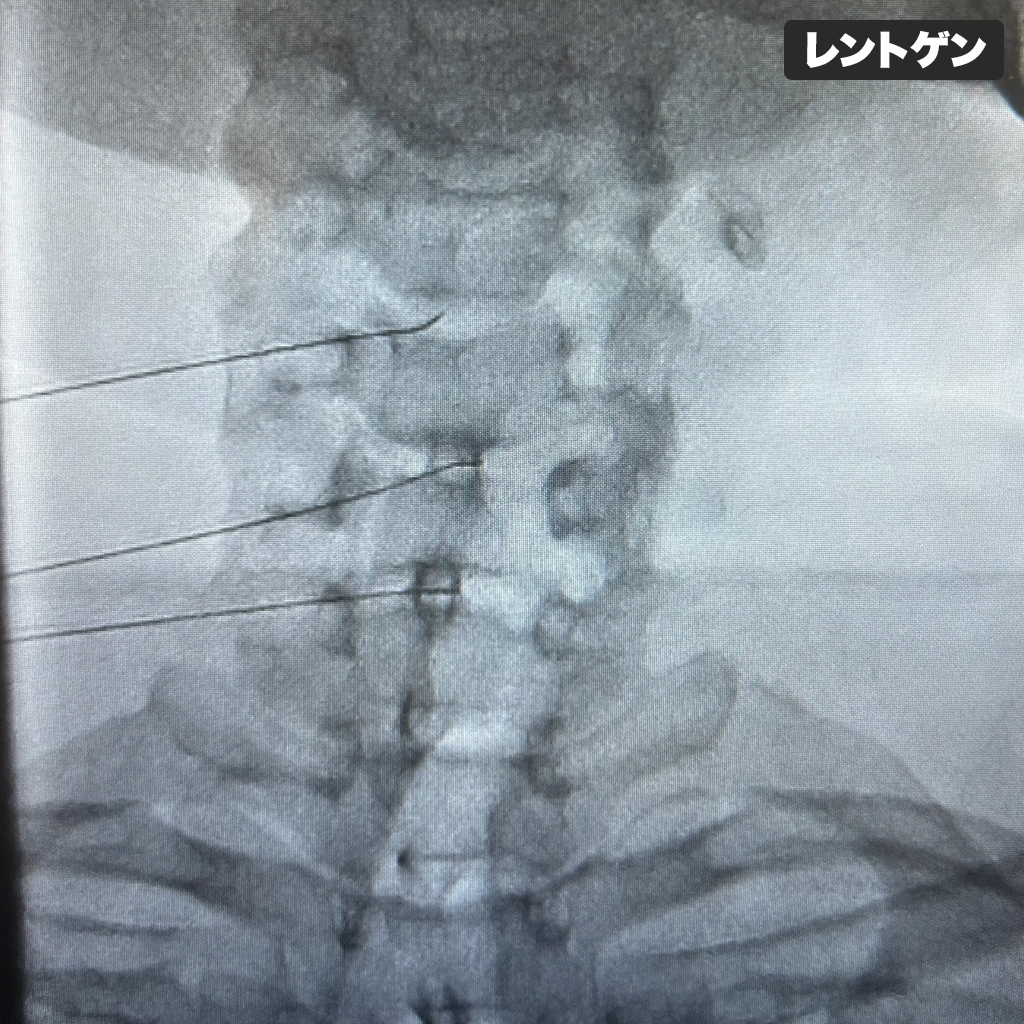

Annulargram

頚椎椎間板のAannulogram(造影検査)で3箇所の椎間板全てにおいて線維輪の損傷を認めましたので、抗炎症治療としてディスクシール治療を行いました。